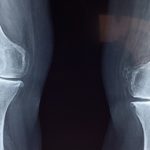

knee